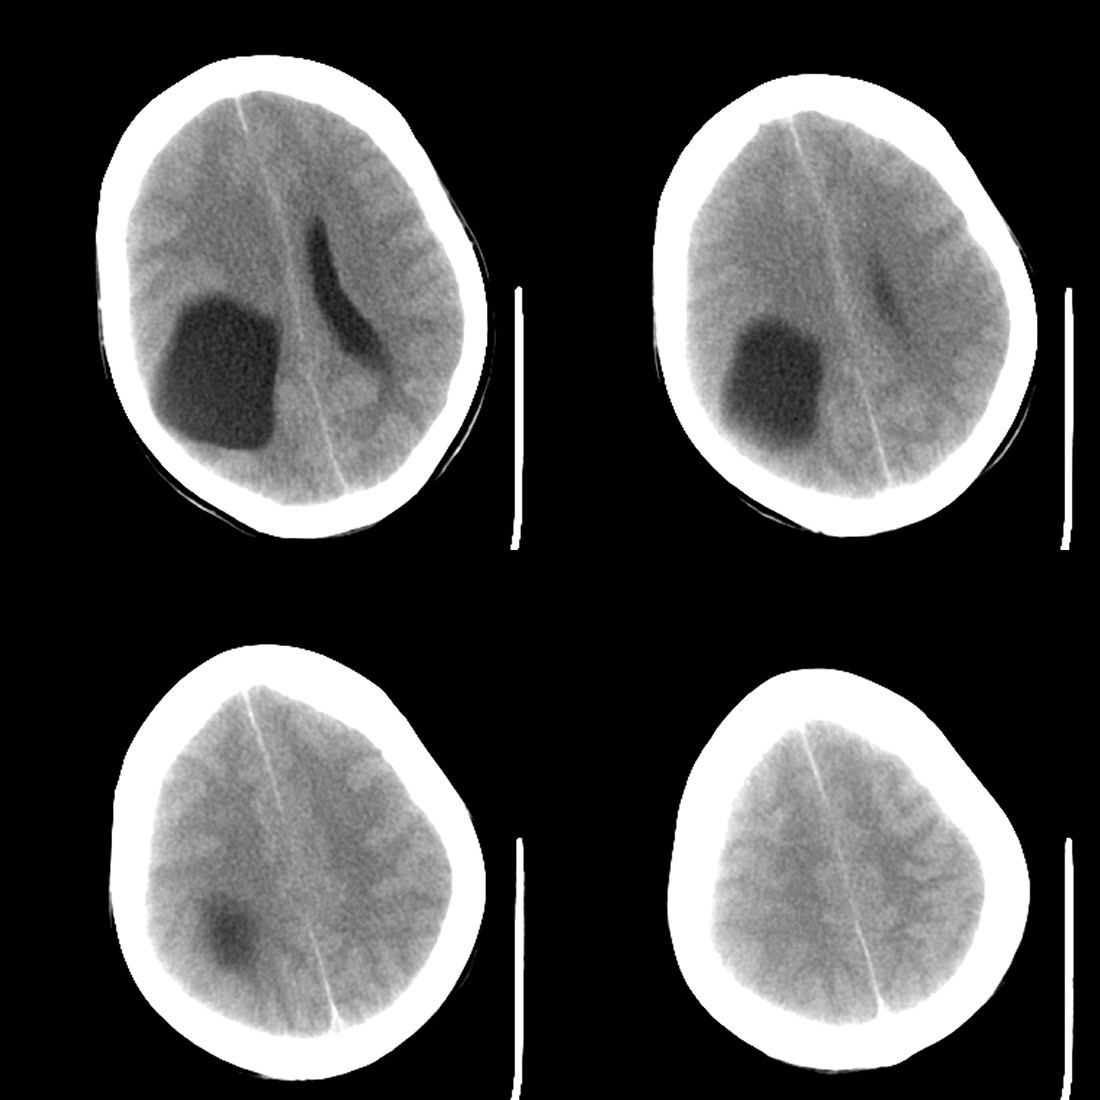

53岁女性,反复头痛,病史较长,今日加重数小时就诊。暂未作增强。

1)考虑蛛网膜下腔出血。2)右侧幕上半球相当于右侧侧脑室三角区区域巨大囊性占位性病变;考虑蛛网膜囊肿,不排除囊性胶质瘤。3)脑积水。4)大脑镰下疝。

考虑蛛网膜囊肿,右侧侧脑室后角及三角区受压变小,中线向左移位。病变与脑室不相通。没有脑积水!!